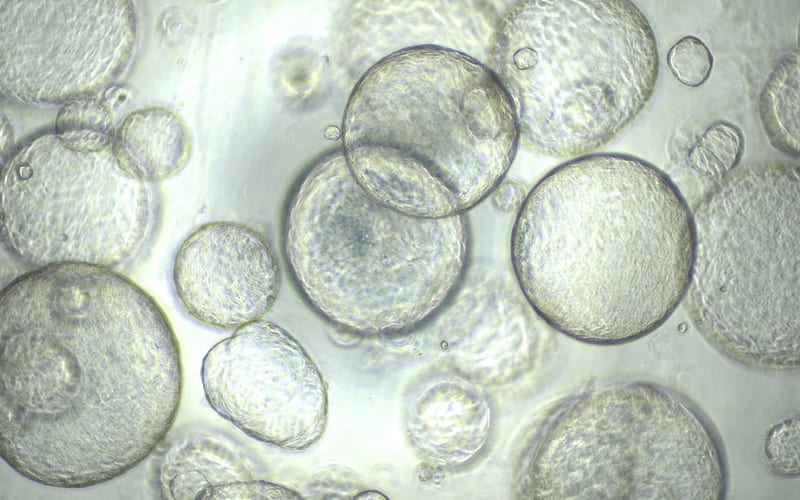

Organoid Technologies

Precision and Scalability

Reliable Results

Empowering Discovery

with Scalable

Organoid Technologies

We transform organoid technology into practical solutions for research,

We are driving innovation through automated technologies for large-scale organoid production, advanced 3D suspension culture methods ensuring reproducibility,

and precision sorting tools, enabling faster drug discovery, accurate toxicity screening, and personalized healthcare solutions.